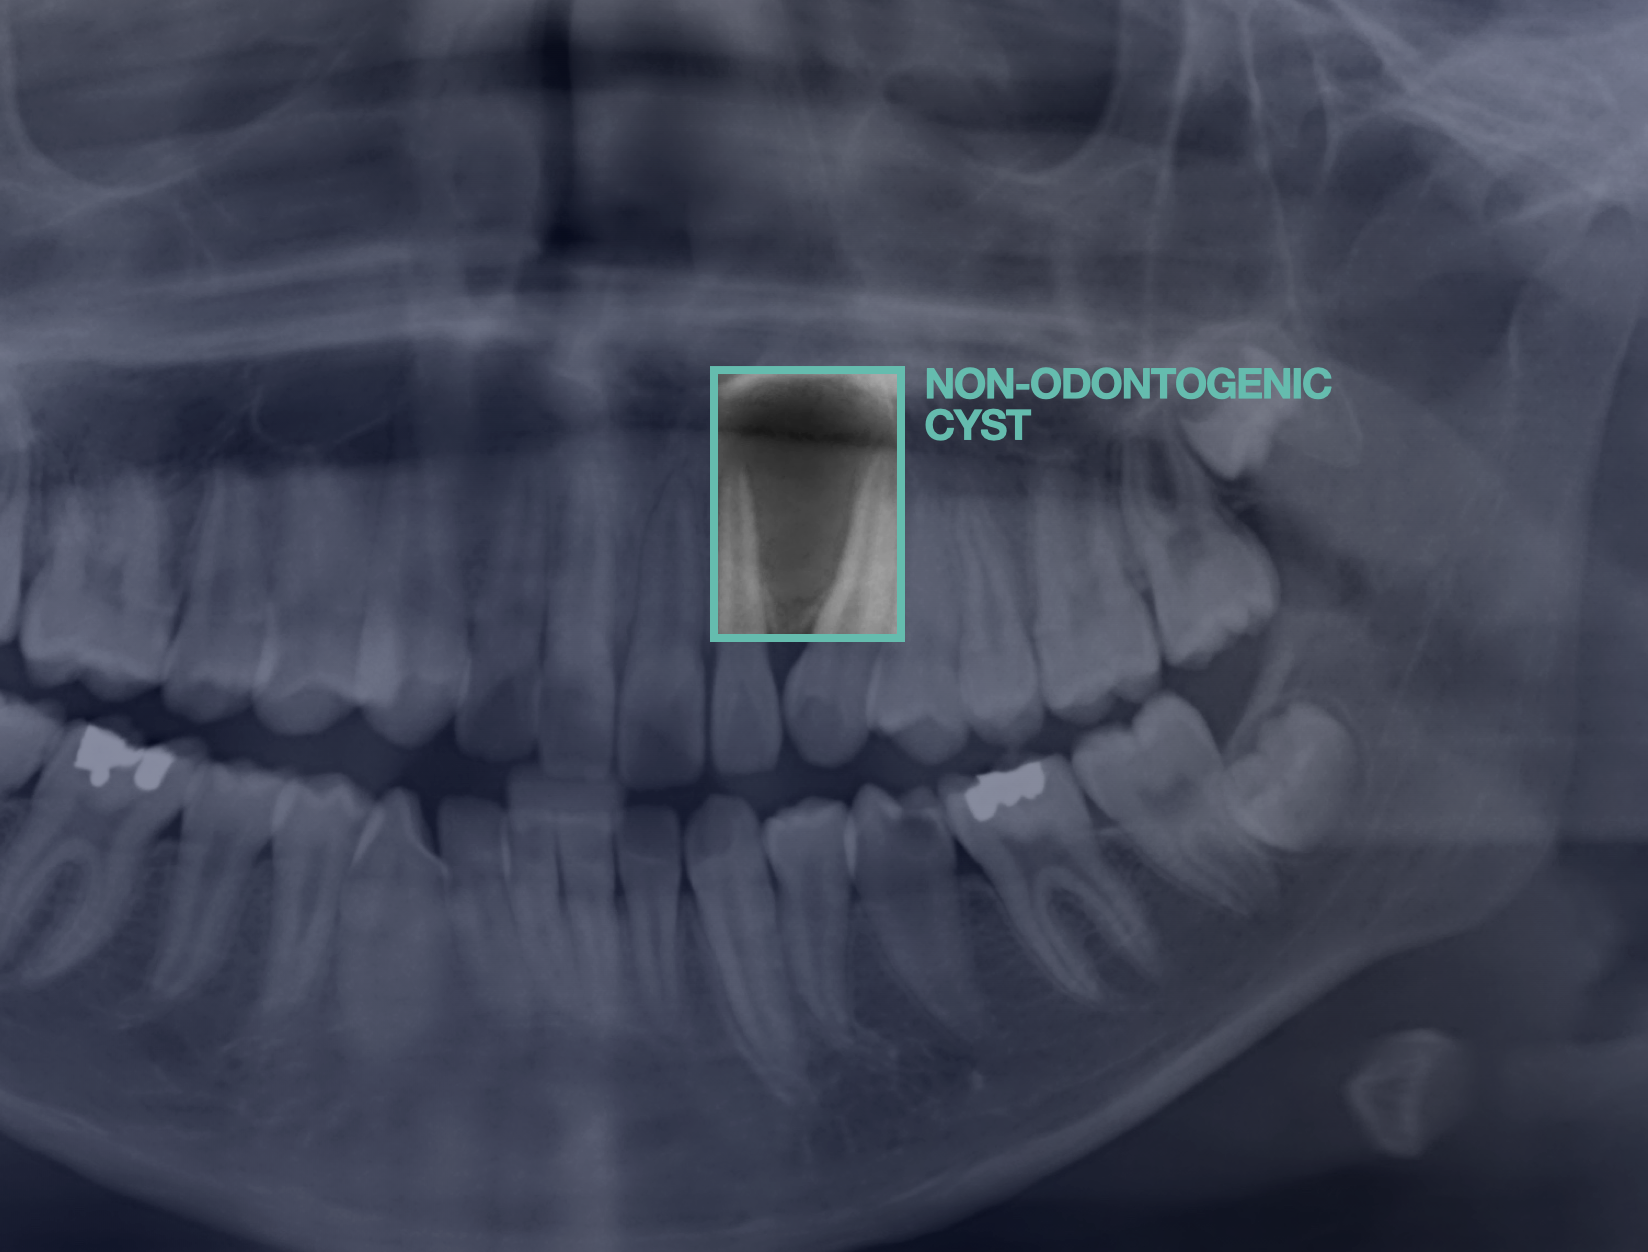

Machine learning models that diagnose jaw cysts and determine whether a tooth is involved.

In this international collaboration between twenty researchers from ten countries, we developed a machine learning workflow that diagnoses jaw cysts and classifies them into odontogenic (i.e., a tooth is involved) and non-odontogenic lesions, thereby aiding the surgical treatment planning process. The models achieved higher diagnostic performance than the international human control group.